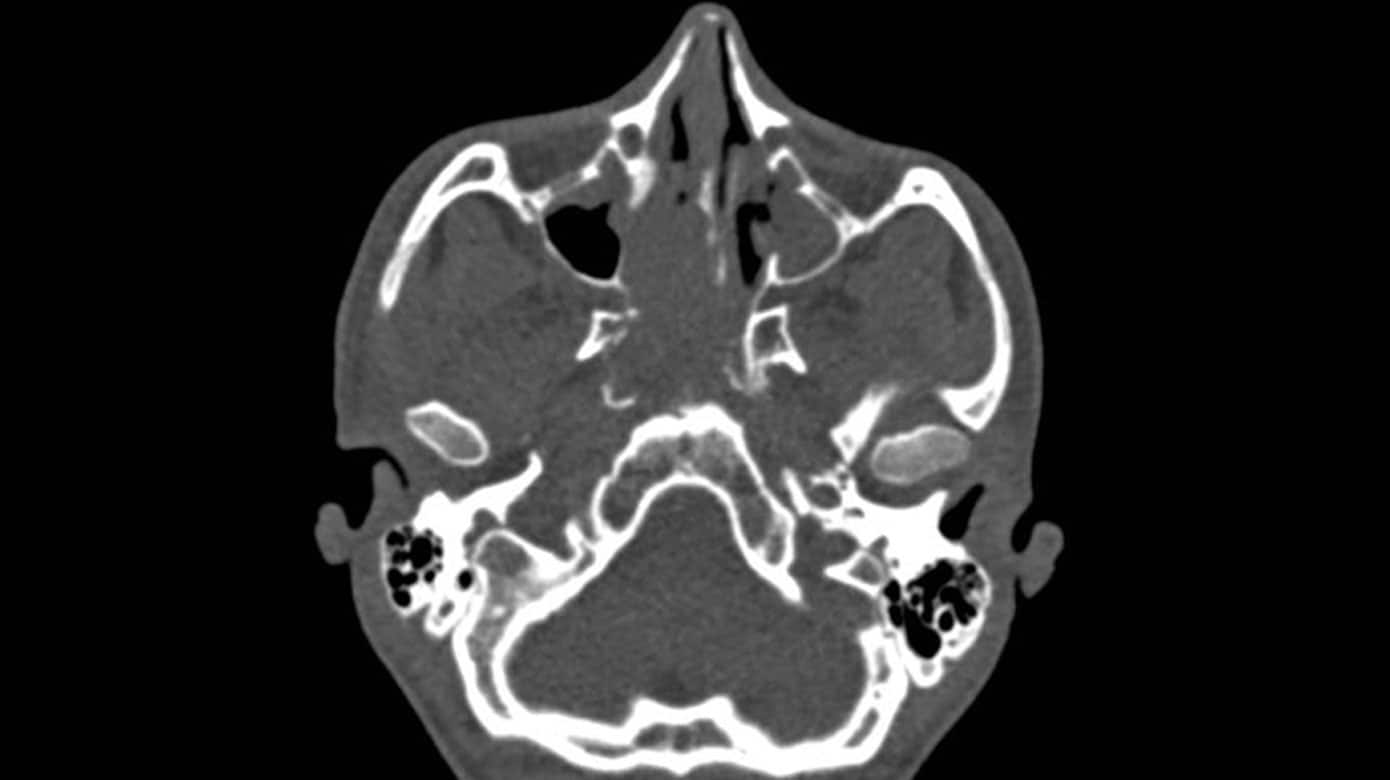

VidenskabVidenskabelig lederØre-næse-hals-specialet i fokus13. okt. 20252 min.StatusartikelAnsigtstraumer i øre-næse-hals-specialet13. okt. 20259 min.StatusartikelImplanterbare høreapparater13. okt. 202511 min.StatusartikelOtitis media13. okt. 202511 min.StatusartikelKirurgisk behandling af hyperparatyroidisme13. okt. 202512 min.StatusartikelSkæv næseskillevæg13. okt. 202511 min.StatusartikelHoved-hals-cancer13. okt. 202512 min.StatusartikelAkutte og kroniske næsebihulebetændelser13. okt. 202511 min.StatusartikelMedfødt hørenedsættelse hos børn13. okt. 202512 min.StatusartikelAkut vestibulær svimmelhed13. okt. 202511 min.StatusartikelHalsabscesser hos børn13. okt. 202511 min.StatusartikelDe hyppigst forekomne sygdomme i balanceorganerne13. okt. 202512 min.

Øre-næse-hals artikler fra Ugeskrift for Læger 20/2025StatusartikelBenigne spytkirteltumorer13. okt. 202512 min.KasuistikIdiopatisk bilateral vestibulopati13. okt. 20255 min.Ugens billedeUspecifikke halssmerter7. jul. 20252 min.KasuistikEksostose ved den indre øregang2. jun. 20254 min.KasuistikKraftig blødning efter biopsi fra nasofaryngealt juvenilt angiofibrom14. jul. 20255 min.StatusartikelNye behandlingsmuligheder for kronisk hoste6. okt. 202513 min.